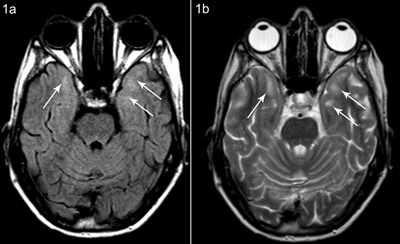

Figure 1

Patient A, axial FLAIR (a) and T2-weighted (b) images at the same level show subcortical white matter hyperintensity anteromedial in the temporal lobes, more pronounced on the left side.